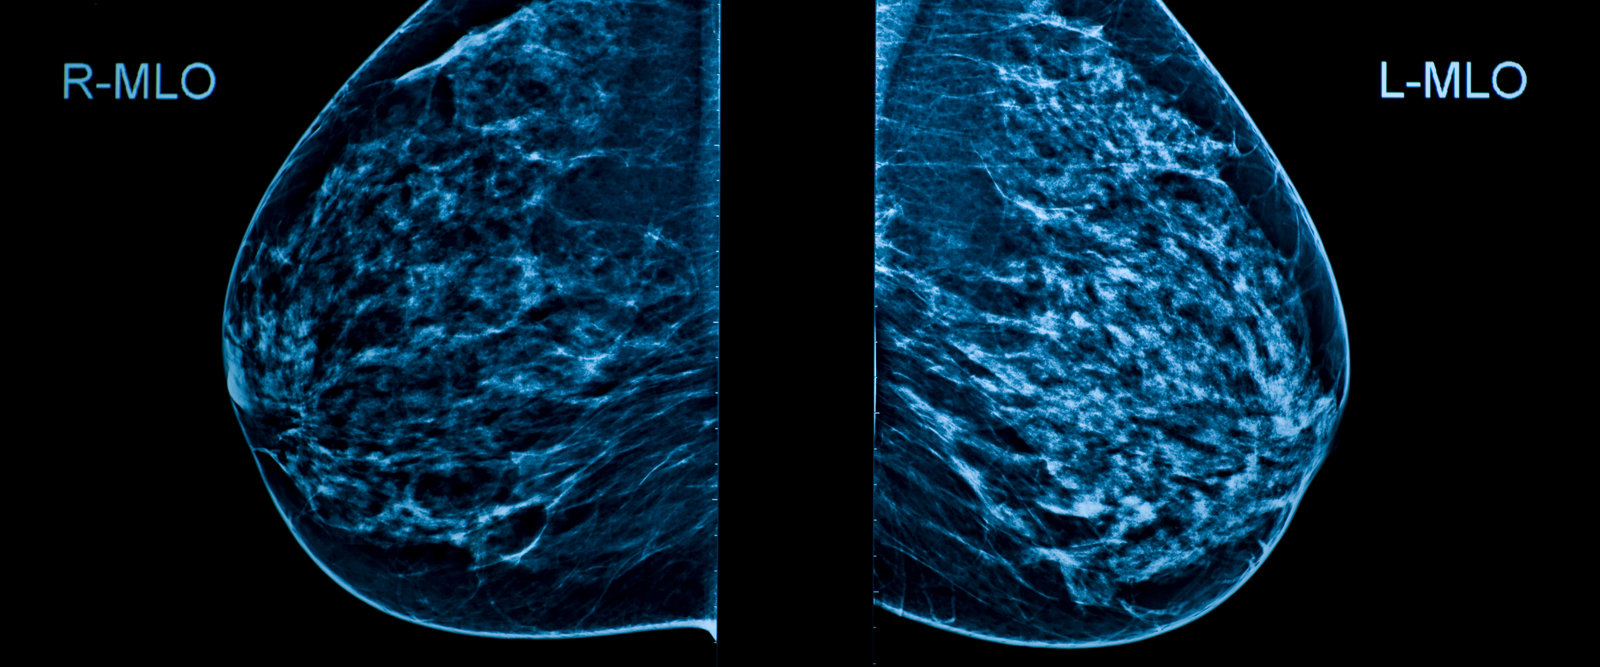

Dr. Reyes: Breast size does not increase your risk, but having dense breasts does. Having dense breasts means that you have higher amounts of fibrous and glandular tissue in your breast and lower amounts of fatty tissue. The only way to have your breast density measured is by doing a mammogram.

It’s important to note that having dense breasts is common. About 50% of women in the U.S. who are 40 years and older do, according to the Centers for Disease Control and Prevention (CDC), so having dense breasts does not mean that you will have breast cancer. It does increase the risk of developing the disease, although it’s not clear why, and makes breast cancer hard to find on a mammogram. That’s why additional screening, such as an ultrasound or MRI, is recommended for women with dense breasts. In the U.S., mammogram centers are now required to notify women of their breast density.